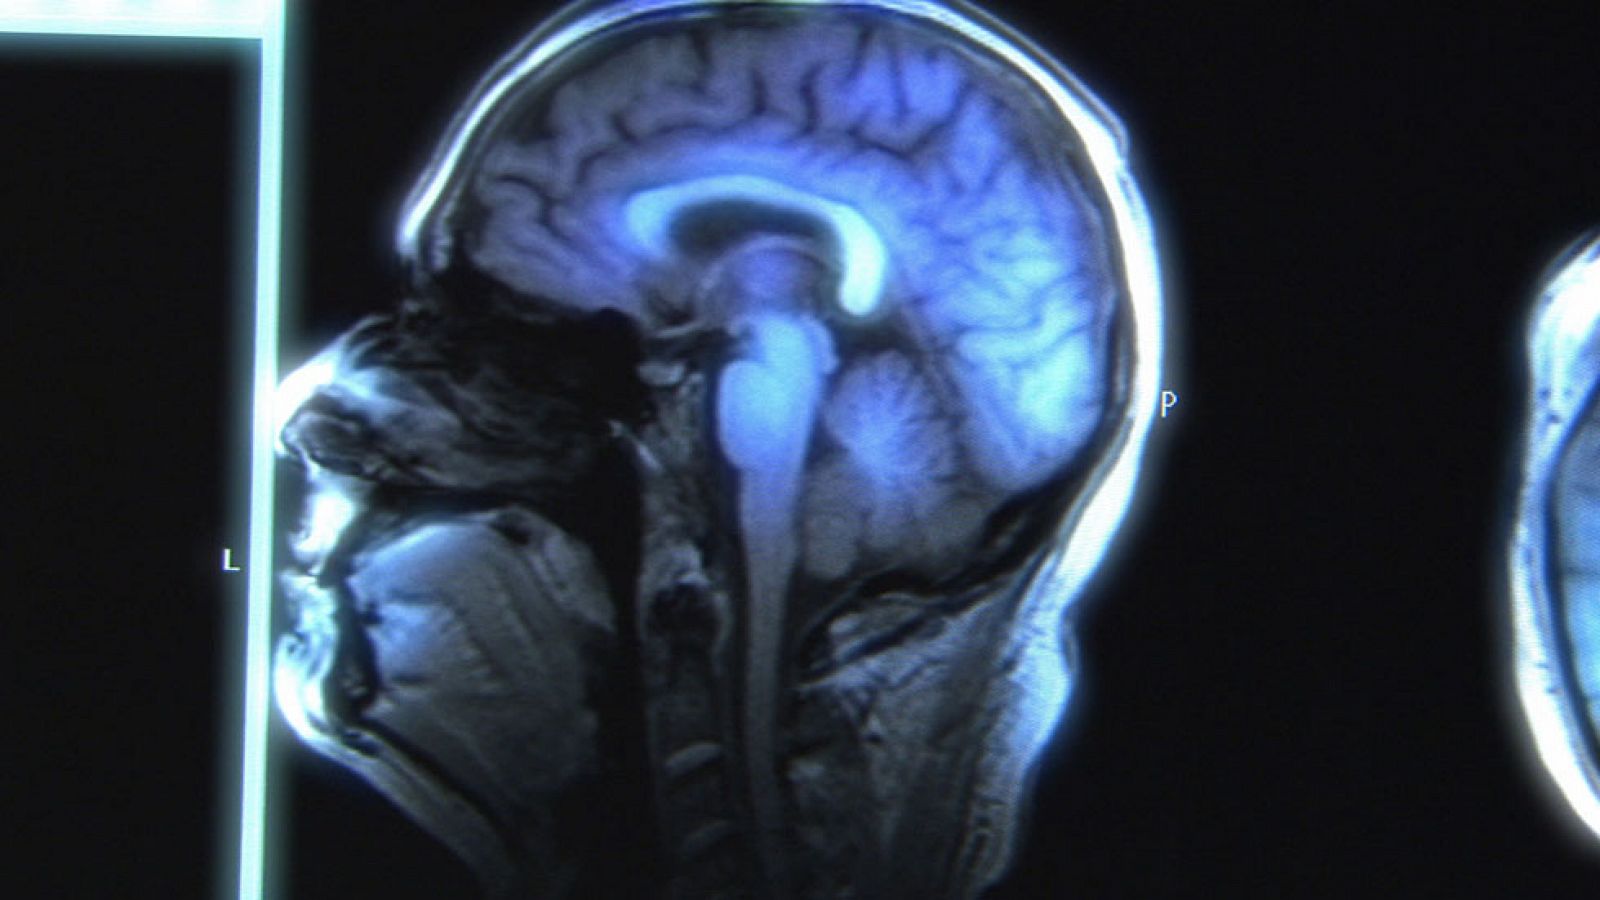

Durante siglos se ha pensado que el cerebro adulto no podía cambiar. Pero ahora sabemos que el cerebro es plástico, es modificable. Hay esperanza...

Durante siglos se ha pensado que el cerebro adulto no podía cambiar. Pero ahora sabemos que el cerebro es plástico, es modificable. Hay esperanza para las personas que sufren daños cerebrales, gracias a la plasticidad del cerebro sabemos que no están condenadas a vivir con ello. La esquizofrenia es una de las patologías beneficiadas, los que sufren esta enfermedad tan incomprendida nos cuentan las claves de su recuperación para acabar con el miedo y el desconocimiento de la sociedad.